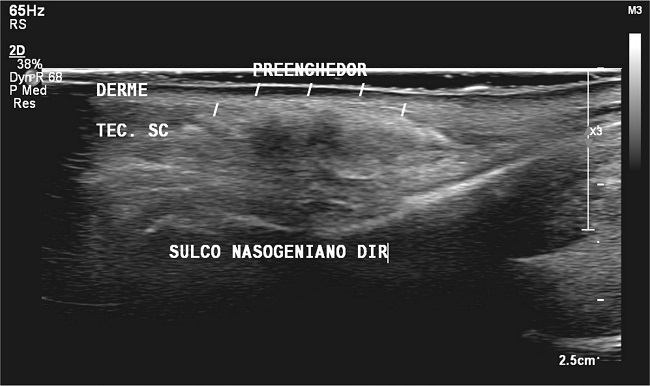

Dermatological examination revealed a well-defined erythematous plaque with an orange background, regular borders, and thin linear vessels at dermoscopy (Figure 1). Complementary investigation showed negative serological markers for rheumatological and infectious diseases. Chest tomography revealed normal parenchyma, with no typical lymph node enlargement. Soft tissue ultrasound revealed hyperechoic deposits with “mini-comet-tail” reverberation artifacts in the region of the nasolabial folds, extending from the height of the mid-nasal third to the labial commissures, suggestive of PMMA deposits in the dermis (Figure 2).